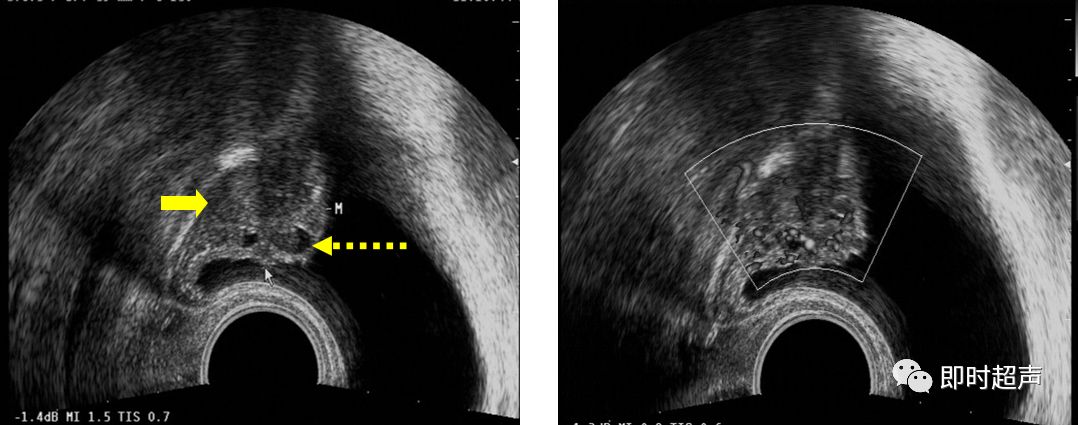

超声表现:

- 膀胱内可见一乳头状、菜花状中、强回声向腔内凸出,肿瘤基底部常较宽,肿物大小不一,表面不光滑,不随体位移动

- 膀胱壁局限性增厚.膀胱壁的正常结构消失,局部连续中断或层次不清晰

- CDFI:显示肿瘤基底部有细条状血流彩色Doppler频谱显示有动脉频谱:RI>0.60

左图:菜花样团状中、强回声(箭头)

右图:CDFI显示显示肿瘤基底部有细条状血流 (箭头)

膀胱壁实性占位

二维 CDFI

膀胱壁多发实性占位

病例3:

患者,女性,35岁,下腹周期性疼痛、肉眼血尿。临床实验室检查:尿常规:镜下血尿。超声声像图如下:

膀胱左侧壁3点处可见团状等回声(箭头),回声不均匀,内见多个液性暗区(虚箭头) CDFI:内无血流信号。

诊断思路:

- 该患者为中年女性,有痛经史

- 超声图像显示膀胱后壁可见一团块状低回声光团,向膀胱内隆起

- CDFI:病变内无血流信号

- 综上所述,诊断应首先考虑膀胱子宫内膜异位症

病理结果:

患者进行了肿块的切除,术后病理:膀胱子宫内膜异位症。